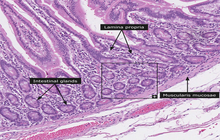

- General and specialized tissue and cell staining

- Prepare educational slides for students from all available tissues

Histological methods includes sample processing in the pathology laboratory, preparation of the slide and its examination under a microscope, sample fixation, molding, microtome cutting, staining and assembly of the slides.